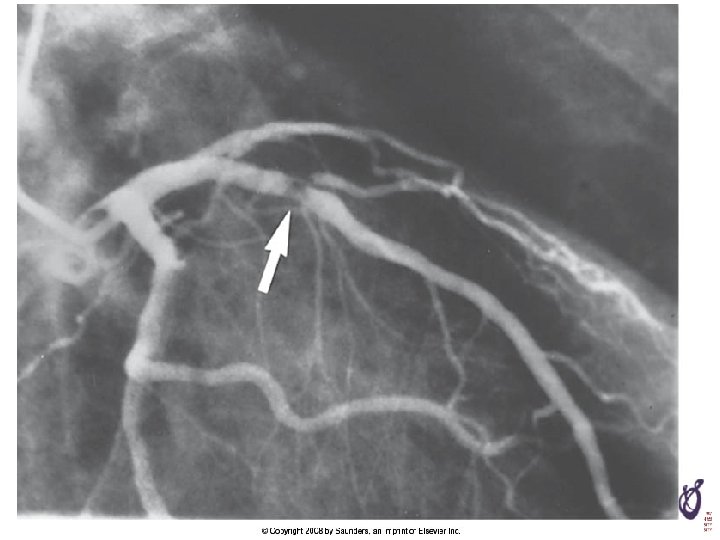

Prinzmetal’s(Variant) Angina o Confirm Diagnosis; • detecting transient spasm by provocative stimulus (i. c. ACH or ergonovine, hyperventilation) on CAG o Long-term survival; excellent n survival at 5 years is excellent (~90 to 95%) o Complications; • disabling pain, MI, VT, AV block, syncope, rarely sudden death

Prinzmetal’s(Variant) Angina initial ergonobine 20 ug 정주 1분후nitroglycerine 정주

Provocation Test